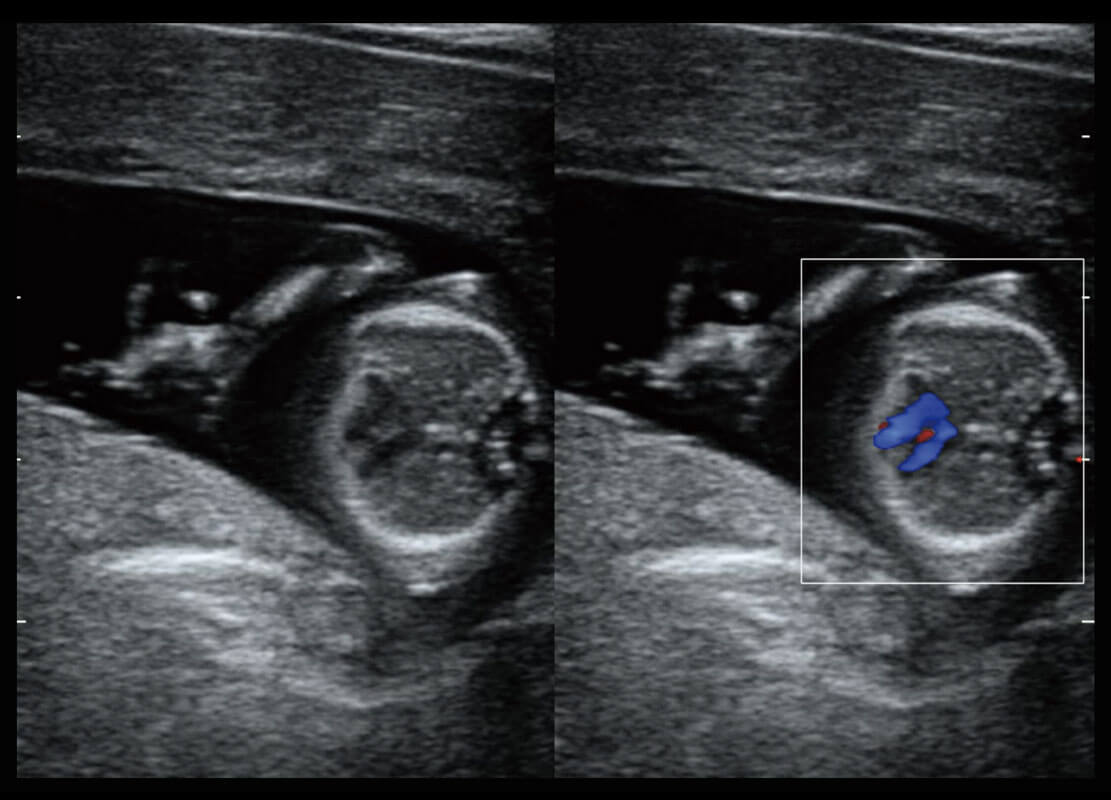

乳腺超声 / 新生儿

P60搭载宽频带线阵探头、宽景成像、弹性成像技术,为您提供乳腺应用方案。P60支持高频相控阵探头、线阵探头、腹部高频探头、腹部微凸探头等,丰富的探头群搭载敏感的彩色血流成像,适用于新生儿多种脏器检测要求,满足新生儿筛查需求。

• 乳腺导管癌

• 乳腺癌显微血流

• 新生儿肝血管癌

• 新生儿脊髓圆锥

• 新生儿心脏